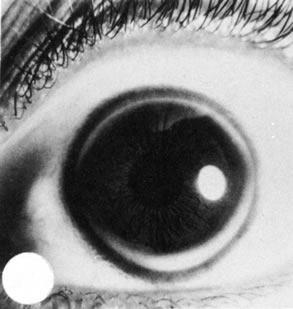

Meesmann's Dystrophy

Meesmann's dystrophy consists of tiny, fine cystlike structures accumulating within corneal epithelial cells, giving the anterior surface of the cornea a multiple oil-droplet appearance (Fig. 25). The lesions are entirely intraepithelial. Although the abnormality usually is manifest in the first decade of life, the degree of cyst formation is relatively stable. This epithelial abnormality generally does not cause decreased vision to more than 20/40. The cysts may rupture at the surface, leading to a foreign body sensation.